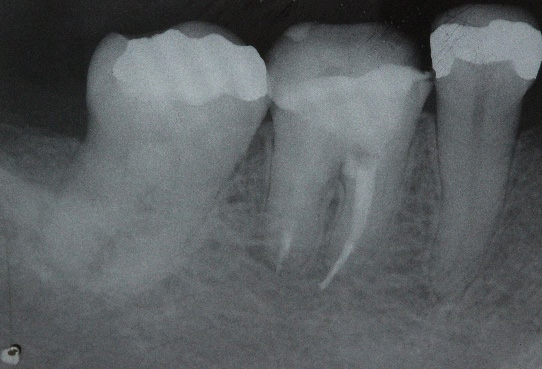

The restoration was removed using a round and conical safe tip bur (Endo Z, Angelus). It was possible to verify the presence of whitish material in the mesial root (Figure 2A). The material was removed, and the perforation was visualized in the distal portion of the mesial root, close to the canal entrance (Figure 2B).

Figure 2: A. Whitish material in the mesial root.

Figure 2: B. Presence of root canal perforation.